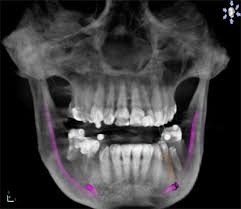

Der eine Nerv ist der Nervus alveolaris inferior der unterste Ast des Trigeminus-Nervs. Hatte ich noch nie eine Spritze im Mund. Weisheitszahn und zyste nerv nah - risiko.

Häufig verläuft ein Nerv entweder durch die Wurzeln oder am Zahn entlang. Und bei nicht wenigen war es der fall dass der eingriff nah am nerv vorgenommen wurde das risiko also da war. Bevor ich meinen körper über jahre mit schmerzmitteln schädige und schmerzen leide würde ich mich diesem eingriff unterziehen.

Sie liegen sehr nah am Nerv weshalb der Arzt nur zwei auf Einmal zieht. Bei der lokalen Narkose besteht das Risiko vor allem dadurch dass durch die Nadel ein Nerv beschädigt wird.